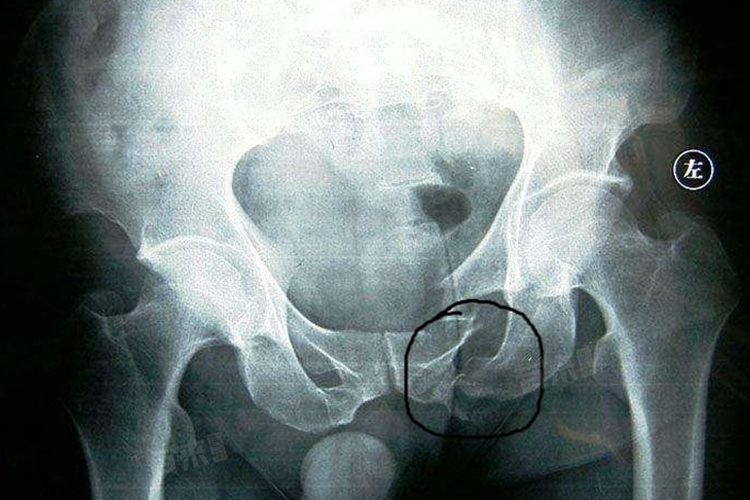

坐骨骨折后能否坐起来不能一概而论,需要根据骨折的具体情况和恢复进度。坐骨骨折初期不能坐起,以免加重损伤;随着愈合,在医生评估下可尝试坐起,需循序渐进;康复后期可正常坐起,但要避免久坐,继续康复训练并定期复查,确保完全愈合无并发症。

- 坐骨骨折初期一般不能坐起来,在骨折后的早期,骨折部位尚未稳定,此时坐起来会对骨折部位产生压力,加重疼痛和损伤,不利于骨折的愈合。坐骨是人体承重的重要部位之一,当坐骨骨折时,周围的软组织也会受到损伤,坐起来会进一步牵拉和刺激这些受损组织,引起剧烈疼痛,还可能导致骨折移位,使病情恶化。